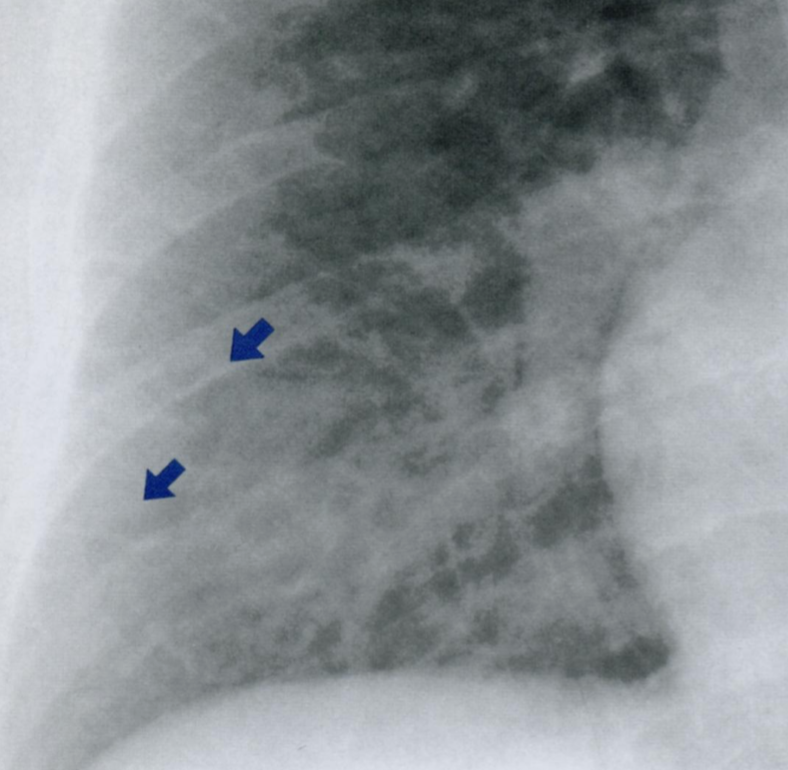

21

Q

Что отмечено стрелками на снимке?

Что такое линии Кёрли? Какие типы Вы знаете?

Интерстициальные заболевания легких характеризуются ретикулоузловой картиной паутиноподобных затенений из-за наложения отечных междольковых перегородок + мелкоочаговых затенений с четкими границами.

A

Поверхностные лимфатические протоки легких, в даном случае с признаками застоя походу междольковых перегородок.

На снимке становятся видны в виде линий, которые мы называем линиями Керли. В даном случае линии Керли типа В (короткие линейные затенения 1-2 см. в сублевральной области (на периферии полей легких) в нижнем или среднем отделе легких.

Линии Керли типа А более длинные (до 5 см.), идут от корней легких в верхней доле.

Есть карточка с делением легких на отделы (отделы - не доли, а как бы три этажа легочного поля, чтобы более понятно описывать локализацию структур именно на снимке).